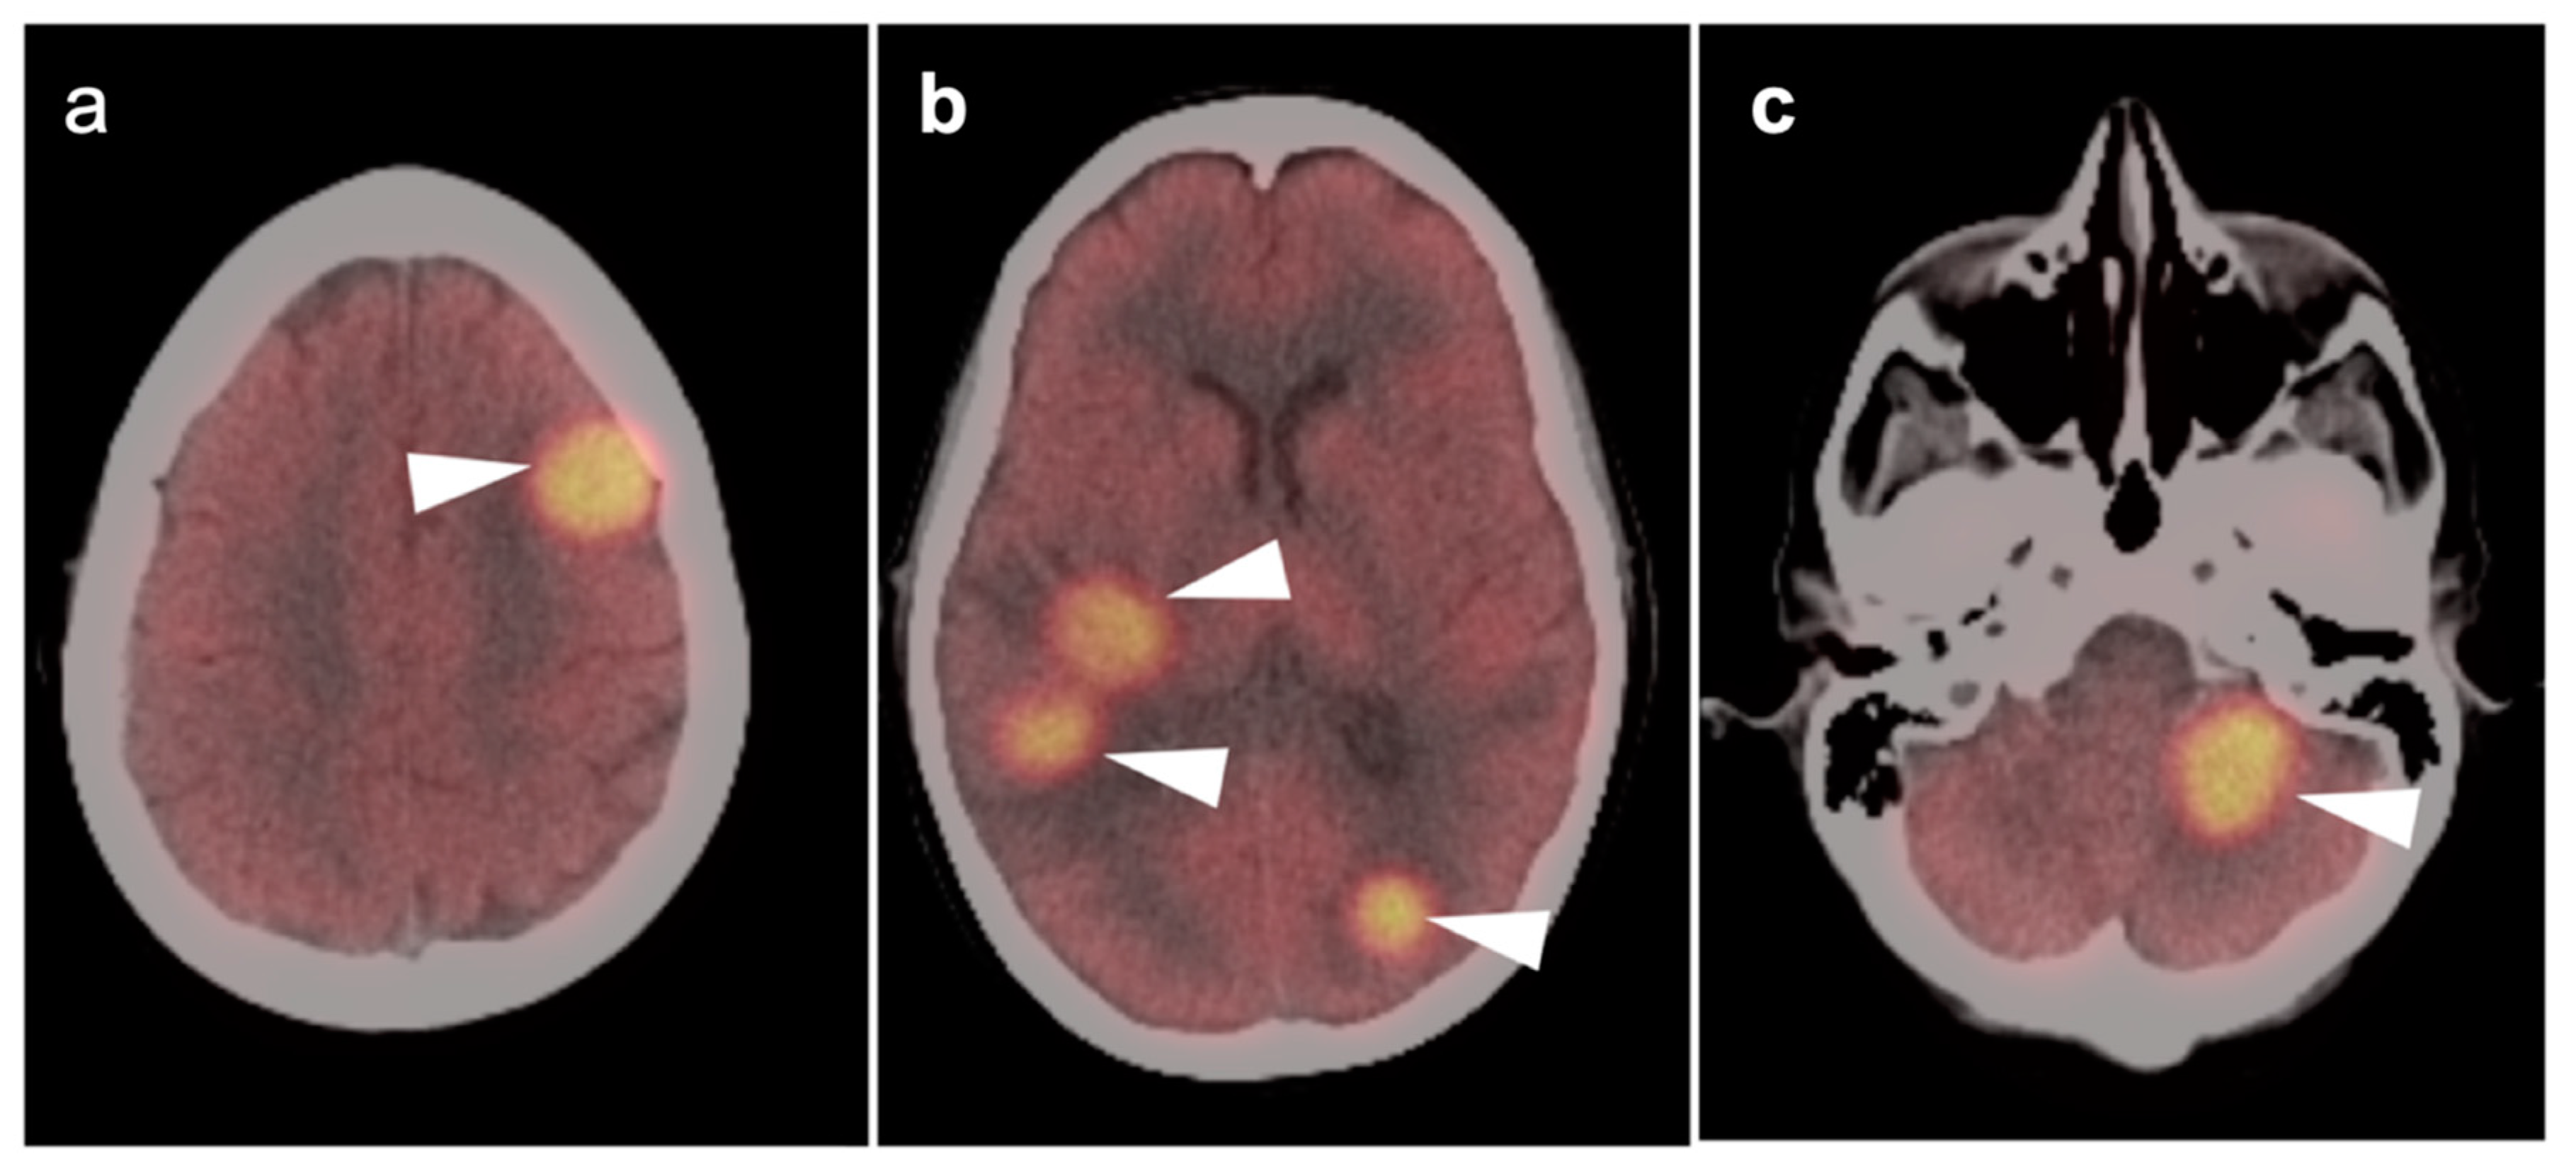

3.5. Brain Metastases

3.6. Response to Therapy